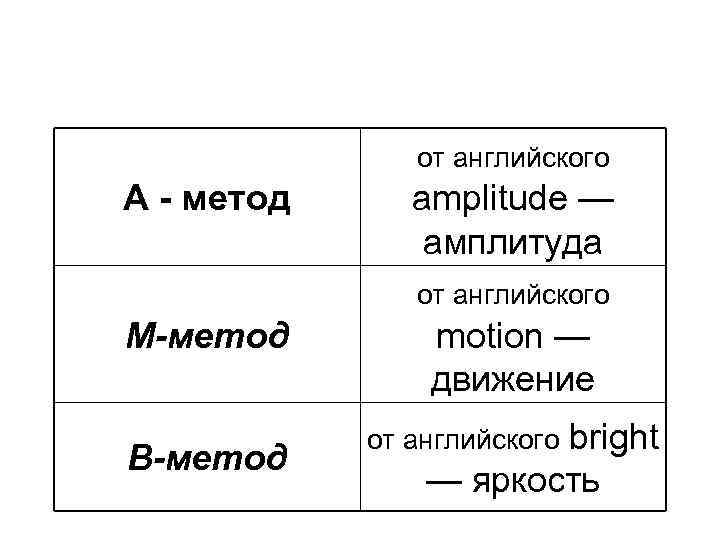

от английского А - метод М-метод В-метод amplitude — амплитуда от английского motion — движение от английского bright — яркость

от английского А - метод М-метод В-метод amplitude — амплитуда от английского motion — движение от английского bright — яркость